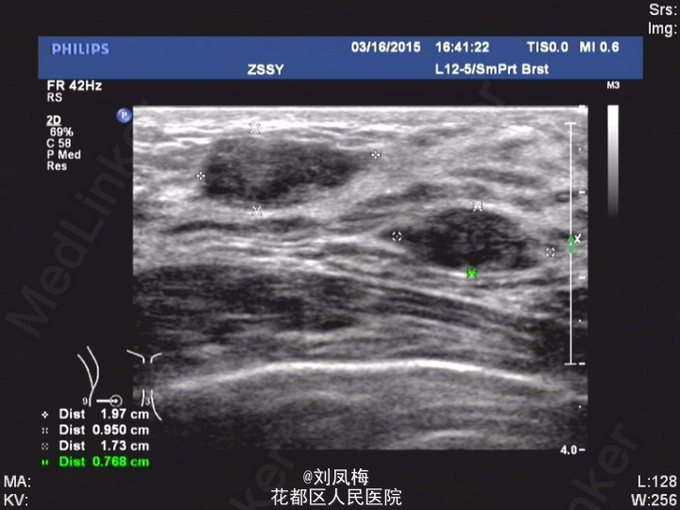

查体:神清,双乳不对称,右乳较左乳稍增大并下垂,右乳9点钟方向可扪及多发结节,较大者约2cm,形态不规则,质中,边界不清楚,按压无疼痛,活动度可。左侧乳房未扪及明显肿物。挤压双侧乳头无液体流出。双侧腋窝未及明显肿大淋巴结。 乳腺B超:双侧乳腺多发实性肿物,BI-RADS 3类(乳腺纤维瘤?)。 双侧乳腺小叶增生声像。 双侧腋窝未见明显异常肿大淋巴结

入院完善相关检查,排除手术禁忌证后于2015-3-17在局麻下行右乳肿物真空旋切术。 术后病理诊断:(右乳肿物)纤维腺病伴腺瘤样结构形成。